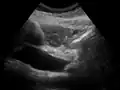

On abdominal ultrasonography, the common bile duct is most readily seen in the porta hepatis (where the CBD lies anterior to the portal vein and hepatic artery). The absence of Doppler signal distinguishes it from the portal vein and hepatic artery.

Borderline of a dilated perihilar bile duct, measuring 8 mm.

Dilatation of CBD due to an ampullary tumor.